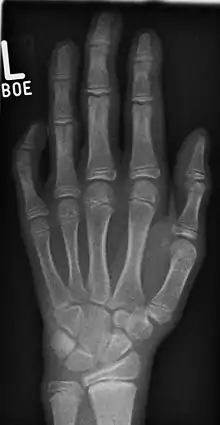

![]() Photograph of a left hand showing severe clinodactyly on the fifth finger. The picture above illustrates a severe case of this condition. | |

يكون العلاج ضروريا فقط إذا كانت درجة الانحناء كافية للتسبب في العجز أو إذا كان تقوس الإصبع يسبب الشعور بالضيق للمريض. غالبا لا تصحح الجبيرة التشوه. ومن العلاجات الجراحية: القص الوتدي المقفول للعظم، والقص الوتدي المفتوح للعظم، وقص العظم الوتدي العكسي،[3] والأشعة على الأصابع مفيدة في التخطيط لإجراء العمليات الجراحية.